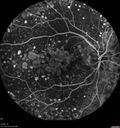

79 year old vision is in for a checkup with no visual complaints in the left eye. This is her better eye. VA 20/200 OD, 20/50 OS. 3 years ago she had a CRVO in the left eye. She is also diabetic for 20 years, has carotid insufficiency and anemia. Left eye shows CME. This was not treated and the vision improved to 20/40 over the next year although mild edema persisted.